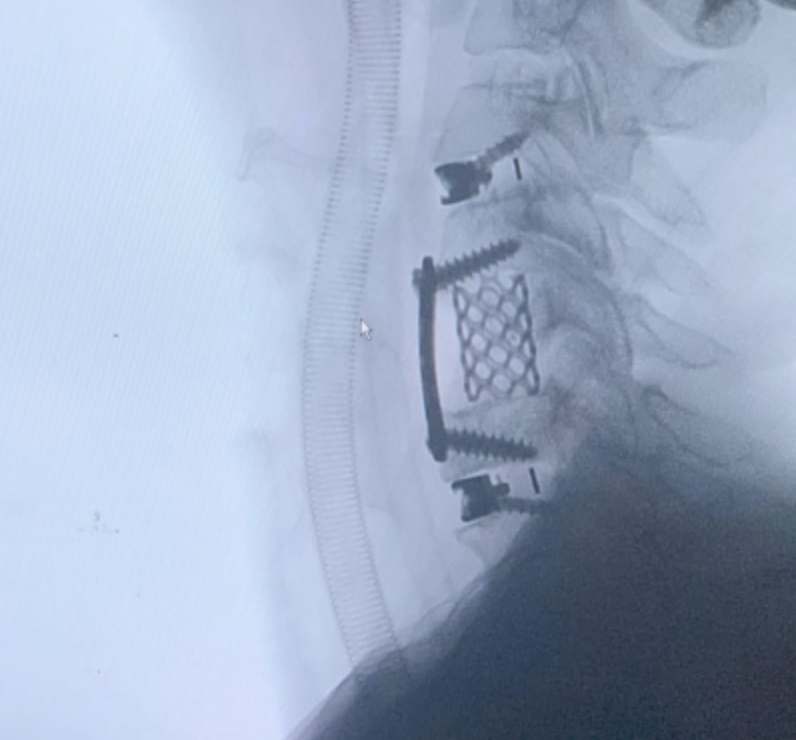

SURGERIES